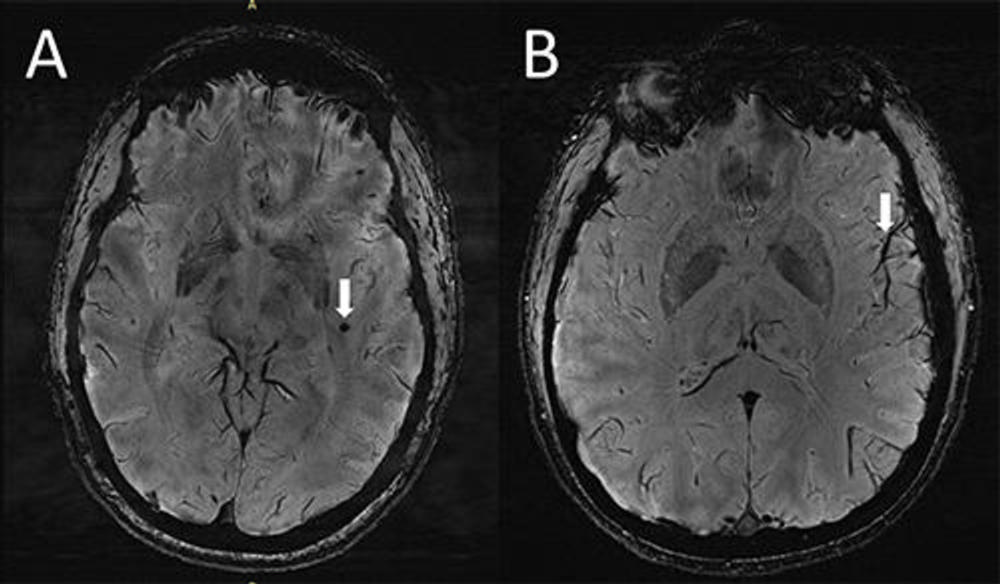

وجد الباحثون أيضًا اختلافًا في توزيع نوع من الآفات المعروفة باسم فرط كثافة المادة البيضاء في مرضى الصداع النصفي، تحدث هذه بسبب بقع صغيرة من الأنسجة الميتة أو الميتة جزئيًا والتي تتضور جوعًا بسبب انخفاض تدفق الدم، وهي طبيعية جدًا.

يعتقد الباحثون، أن هذا يشير إلى أن توسيع المساحات المحيطة بالأوعية الدموية؛ يمكن أن يؤدي إلى تطور مستقبلي لمزيد من آفات المادة البيضاء.

ورغم أن طبيعة العلاقة بين تضخم المساحات المحيطة بالأوعية الدموية والصداع النصفي غير واضحة، فإن النتائج تشير إلى أن الصداع النصفي يأتي مع مشكلة في أنابيب الدماغ الجهاز الليمفاوي المسؤول عن التخلص من النفايات في الدماغ والجهاز العصبي، ويستخدم قنوات حول الأوعية الدموية للنقل.